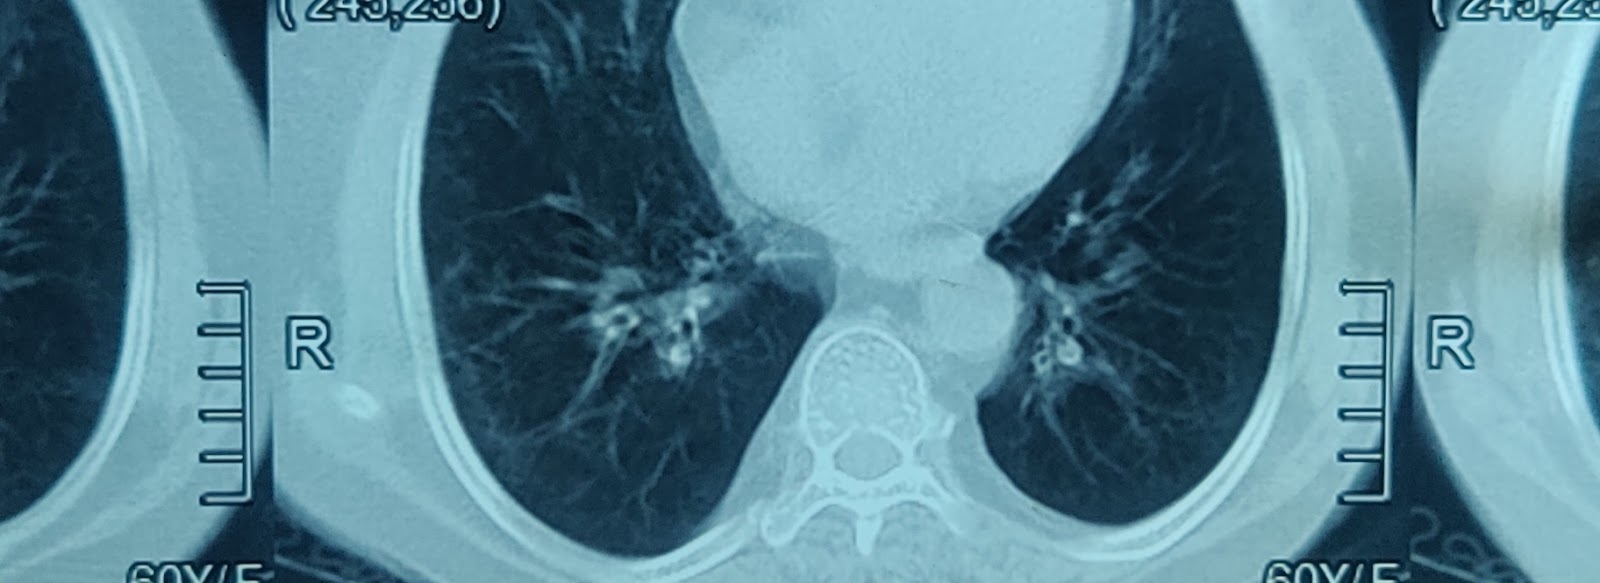

?Right sided bronchiectasis ?COPD ?chronic bronchitis associated with diabetes mellitus

Chest x ray